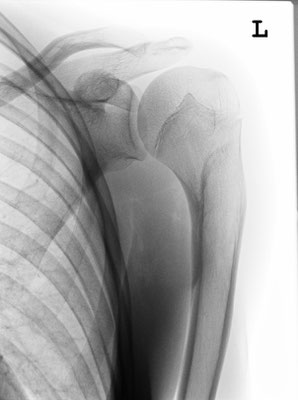

13-jähriger Junge mit Oberarmkopfbruch (Abb.1). Nicht operative Behandlung. Abb.2 zeigt das Röntgenbild nach 1 Jahr. Abb.3 zeigt die Funktion nur 2 Monaten nach dem Unfall!